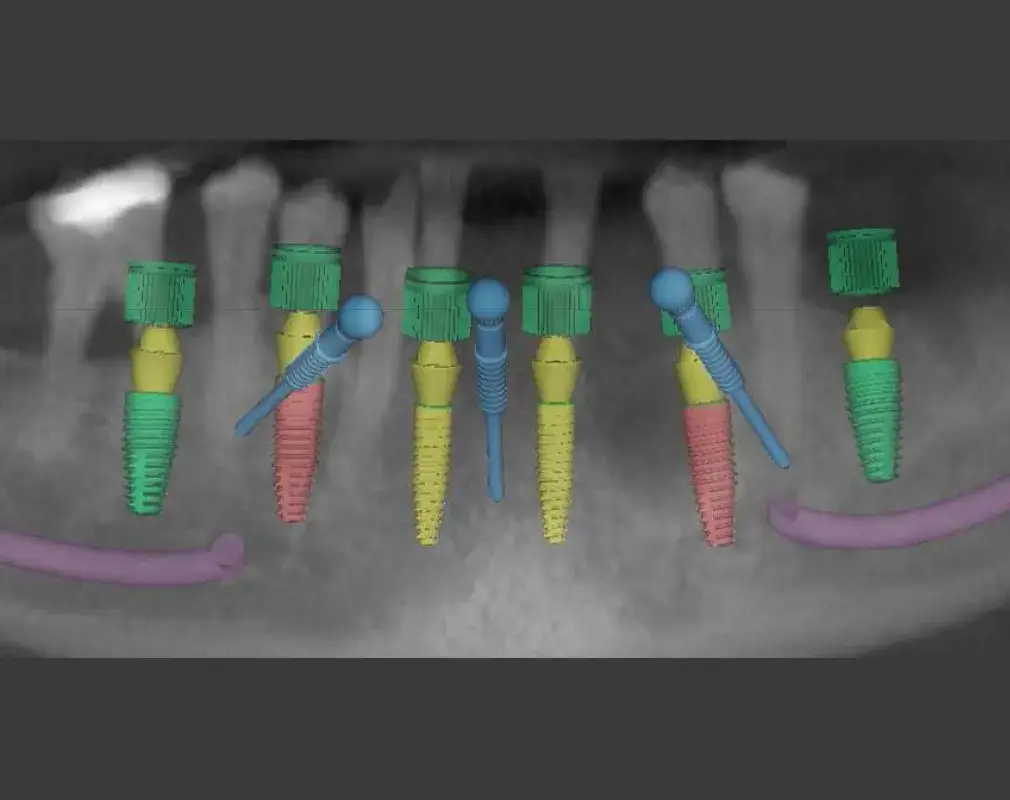

- Digitale Präzision: Mithilfe unseres 3D-Scanners erfassen wir jede Nuance Ihres Kiefers.

- Geführte Chirurgie (Schablonen): Wir planen den Eingriff am Computer vorab bis ins kleinste Detail. Durch den Einsatz individuell gefertigter Bohrschablonen setzen wir die Implantate exakt dort, wo sie biologisch und ästhetisch hingehören.